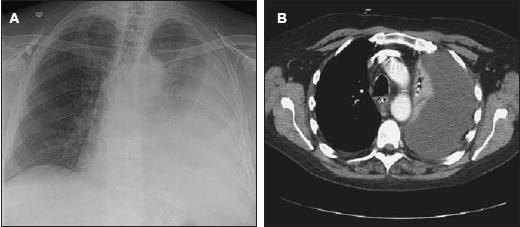

Four days later, the ileus improved with nasogastric tube suction and enemas, but the WBC count increased to 20.5 × 103/μL, with 27% bands. The patient complained of dyspnea, and his oxygen saturation was 92% on room air. A second chest radiograph and a CT scan of the chest demonstrated a large left-sided effusion with left lung collapse (Figure 3).

Figure 3 – A large left-sided effusion with left lung collapse was found on a second chest radiograph (A) and a CT scan of the chest (B).